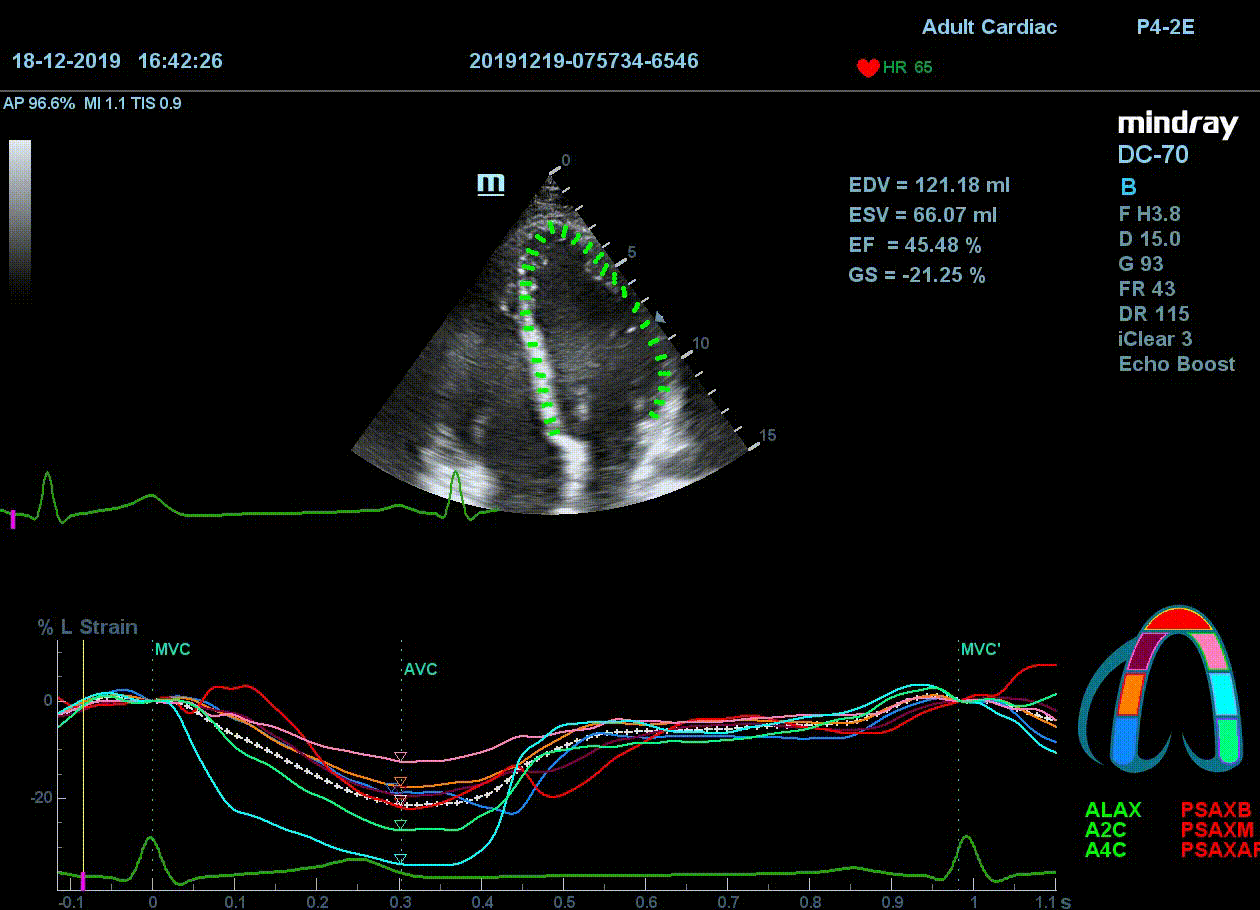

Как работать с данным методом? Для Longitudinal Strain необходимо записать видео петли апикальных сечений в память прибора: 4С, 3С, 2С. Для повышения качества трекинга рекомендуется производить запись на выдохе пациента. Затем произвести разметку по линии эпикарда, перикарда и центра миокарда. Нажатием кнопки «начать слежение» активируется программный алгоритм, видео петля оживает вместе с размеченными точками-speckle’ами. При необходимости производится коррекция. После анализа всех трех сечений можно получить данных продольной деформации как в среднем значении, так и по каждому сегменту миокарда левого желудочка. Нормальным показателем считается Longitudinal Strain -20%. Нижней границей -14%.

Видео примеры на приборе Mindray DC 70